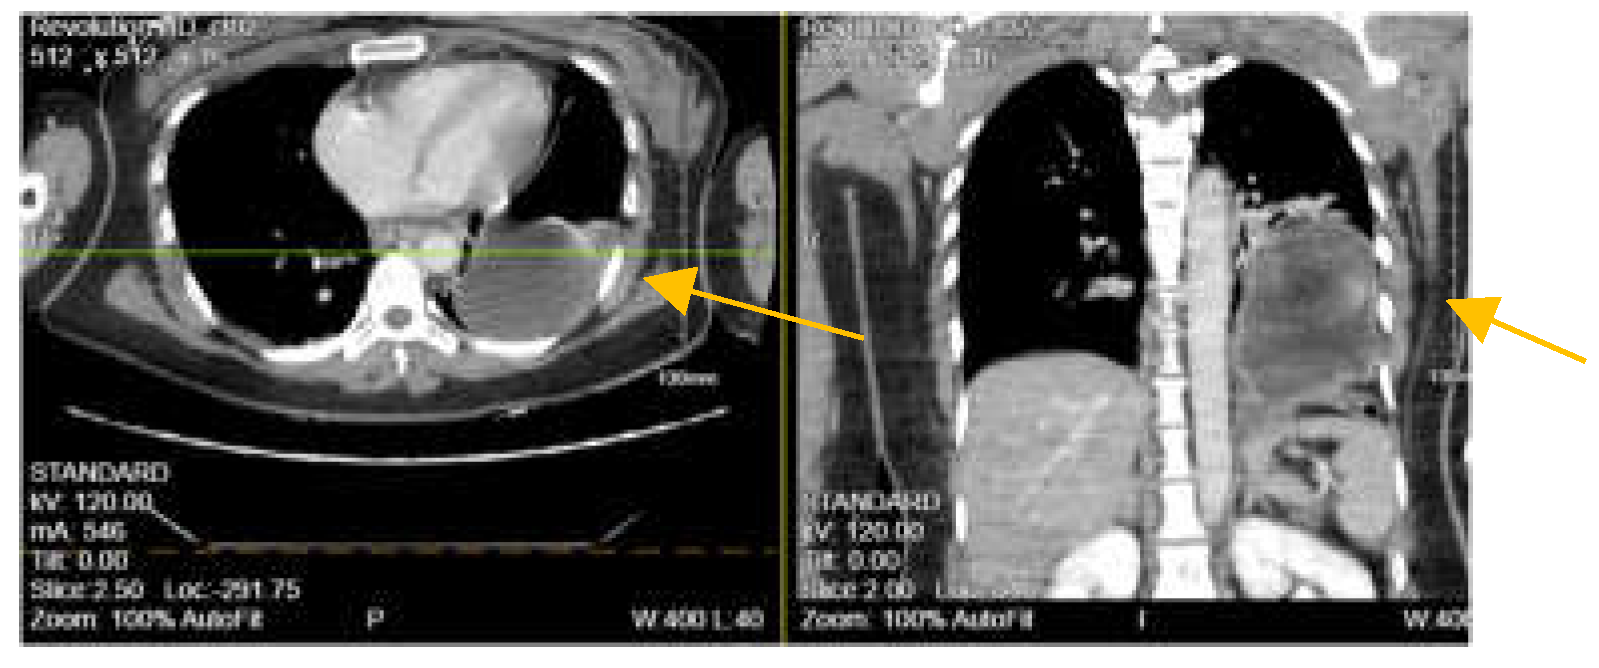

An 88-year-old White American woman with a past medical history of hypertension, hyperlipidemia, and hip fracture with repair (4 years ago) presented to our emergency department (ED) with complaints of pain in her right forearm, left hand, lower back, and on the chest bilaterally with trouble breathing. According to the patient, she fell at home 2-days ago. She did not remember how she fell or the precise location but believed she tripped. The patient admitted to an extensive smoking history and likely has undiagnosed chronic obstructive pulmonary disease (COPD). Denied any loss of consciousness, dizziness, or hitting her head. The electrocardiogram (EKG) finding was significant for rapid atrial fibrillation (no prior history) which was managed with an anti-arrhythmic medication throughout her hospital course. The patient was tachycardic, tachypneic, hypotensive with blood pressure (BP) of 96/62 mmHg, and hypoxic to 88% for which she was placed on supplemental oxygen but afebrile in the ED. Physical examination noted tenderness to the right lateral chest with bruising to the right breast and right forearm with an overlying laceration. The abdomen was soft and non-tender. No sign of labored breathing. Chest X-ray (CXR) revealed right pleural effusion and areas of atelectasis with several right and lower fractured ribs. Contrast-enhanced computed tomography (CT) of the chest showed a perforated right hemidiaphragm with gastrointestinal content in the thorax (Figure 1A). CT abdomen and pelvis revealed no acute findings. The patient refused surgical intervention. Two days after admission to the surgical intensive care unit (SICU), the patient experienced respiratory distress with the use of accessory muscles to breathe and became hypotensive for which she responded to fluid resuscitation. CT angiogram (CTA) was performed which showed herniation of the bowel into the right anterior chest significantly compromising the right lung volume, pleural effusion, and small pneumothorax (Figure 1B). The patient again refused surgical management and signed a do not intubate and do not resuscitate (DNI/DNR) order. The patient requested comfort care only and died the next day from her condition. Injury Severity Score (ISS) was 29.

Figure 1. (A) Contrast-enhance computed tomography (CT) of the chest showing a large right diaphragmatic hernia containing hepatic flexure of the colon and omental fat without evidence of strangulation (blue arrow). (B) CTA revealed a large intestine in the right chest consistent with worsening herniation with the right lung completely collapsed by the herniated colon.